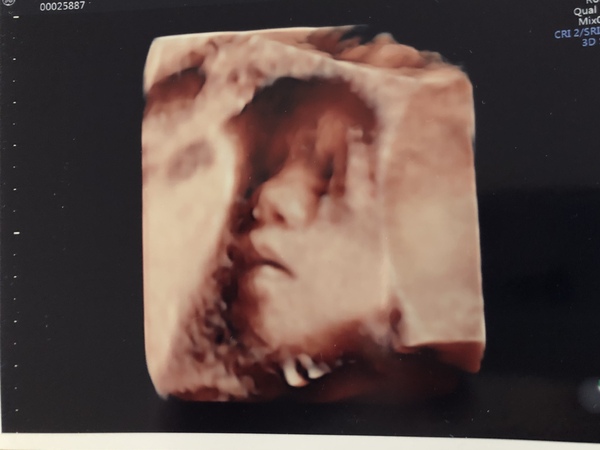

@newbyxx also FTM here but my bump is still very low too. Had a scan today and baby’s head is right down the bottom and she’s all curled up so I barely feel any movements higher than my belly button. I do, however, feel lots of jabs to my cervix and bladder which is always fun 😣

Happy today because GTT came back normal, baby is growing fine, and I got a cute photo of her face. I think she looks like my husband and my husband thinks she looks like me lol. Can’t wait to see her in real life!

27+0